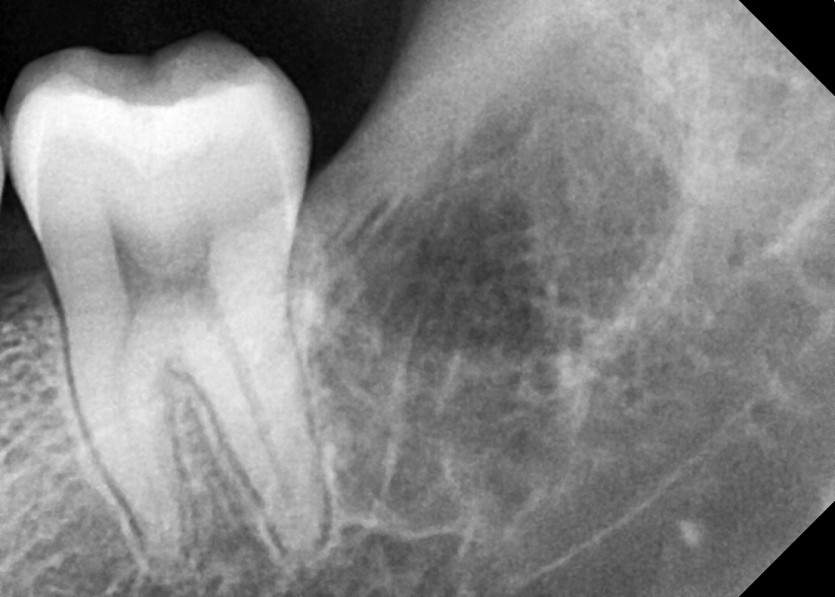

#28,38,48 사랑니 발치

구강 외과 전문의가 당일 발치했습니다.